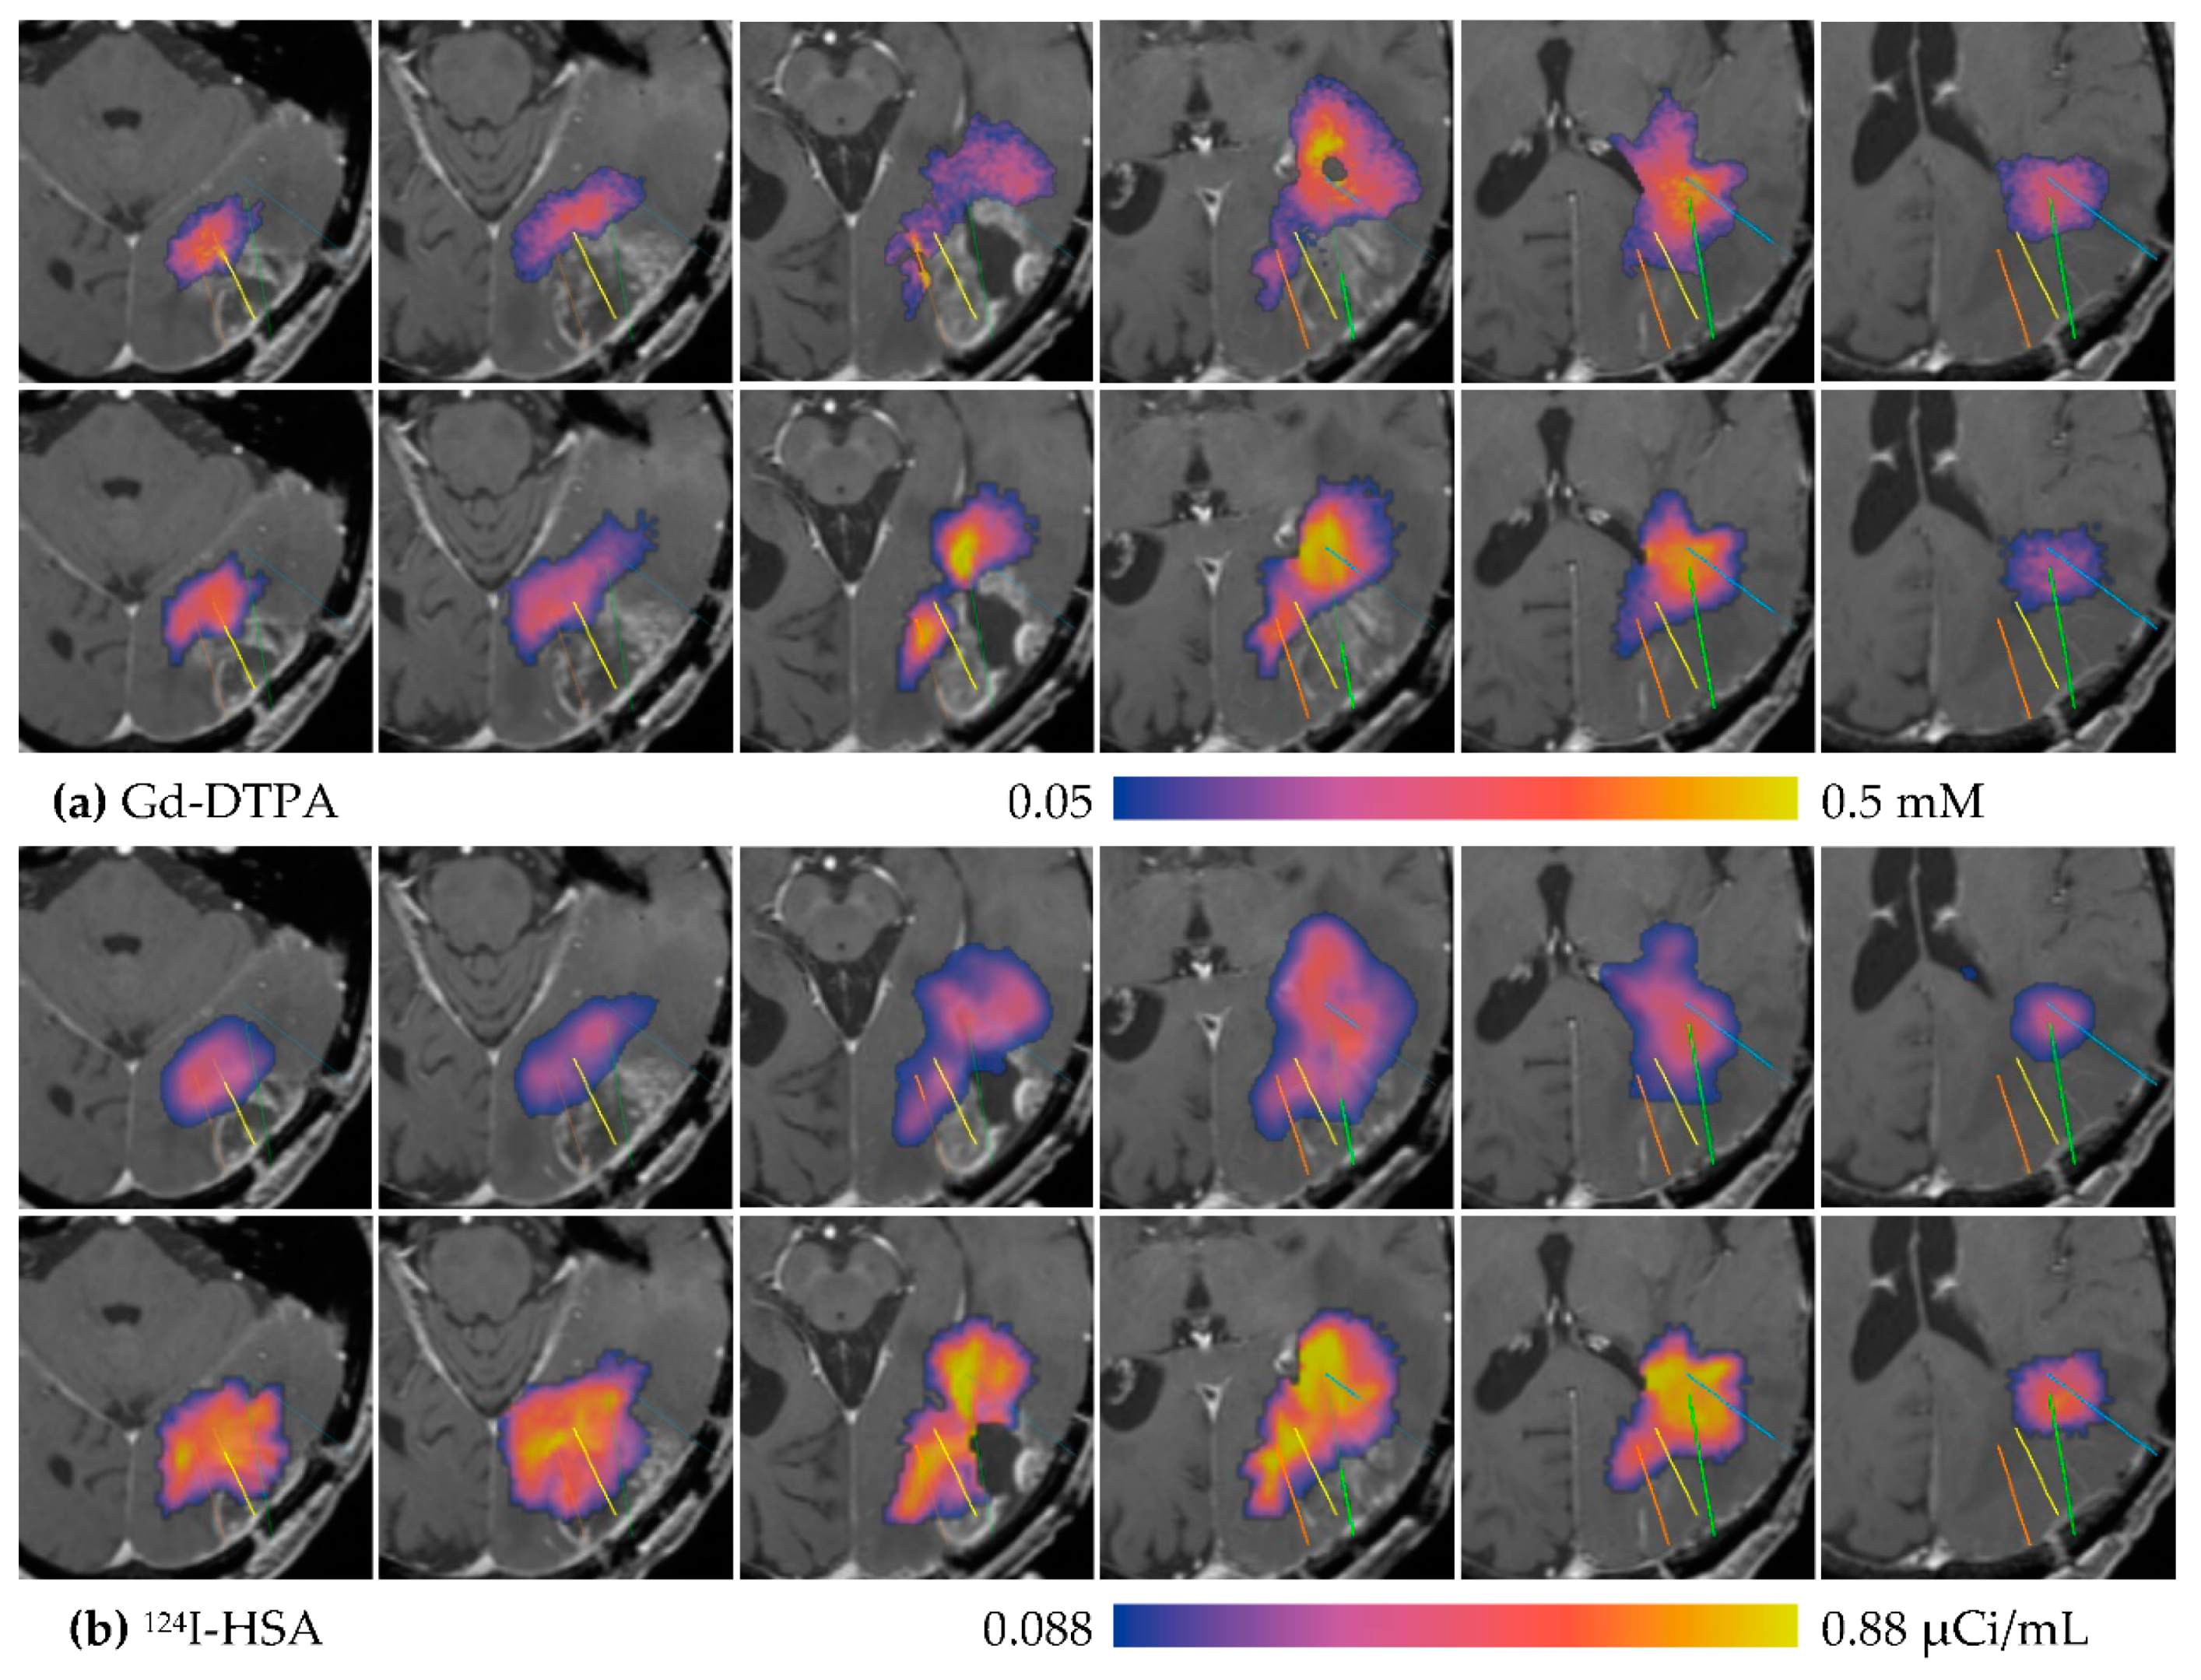

3.1. Descriptive Results

3.2. Statistics of Infusions and Simulations

3.2.1. Total Distribution Volume